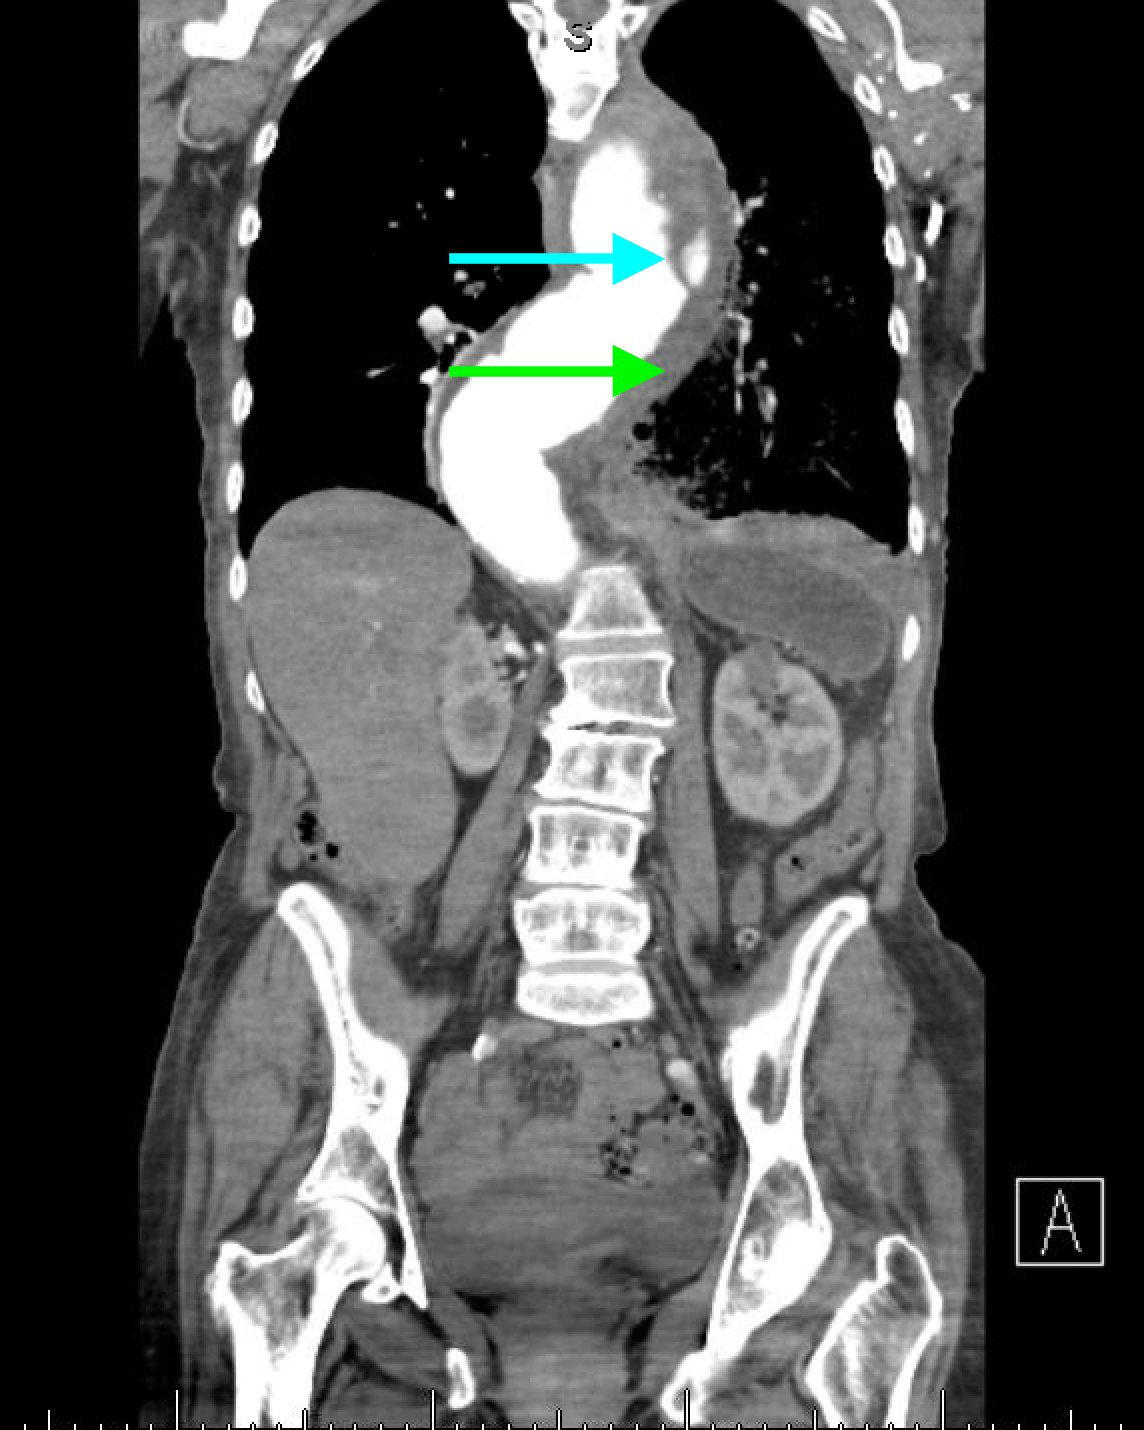

The patient’schest X-ray revealed a prominent mediastinum and opacification in the left middle and lower lung fields. The CT showed an aortic aneurysm extending from the thorax to the abdomen with rupture near T7 (blue arrow). It also showed periaortic hemorrhage with active extravasation (green arrow) likely secondary to a penetrating ulcer and bilateral pulmonary opacities concerning for hemothorax (pink arrow).